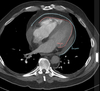

95

TEP

96

4 = trombo

97